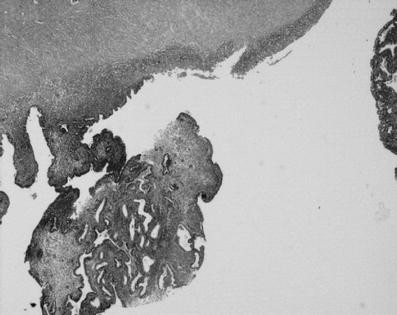

Foci of adenocarcinoma with sarcomatous component and areas of necrosis

Cystic endometriosis and areas of atypical hyperplasia

Oophorectomy was performed laparoscopically. During the mobilization of the ovary, spillage of the cystic content happened. Definitive histology showed microscopic endometrioid adenocarcinoma with foci of solid and clear cell carcinoma, grade 3, within an ovarian endometrioid cyst. One month later, she underwent a laparoscopic restaging: peritoneal washing, hysterectomy, omentectomy, and random biopsies with para-aortic, infra, and sovra mesenteric and pelvic lymph nodes sampling were performed. Histology was negative in all the samples, including 15 para-aortic lymph nodes and 11 ipsilateral pelvic lymph nodes. Finale stage was pT1c because of the spillage. Even if the chemotherapeutic management of pT1c and third stage ovarian cancer is the same, we considered it important to have data about cytology in the peritoneum after spillage and about the lymph nodes. The patient received six cycles of carboplatin–Taxol combination as adjuvant chemotherapy. At 2 years follow-up, she was well with no evidence of disease.

The combination of these two histotypes was found in our first patient. Carcinosarcoma, which we found in our second patient, is considered a rare variety. Both tumors are very aggressive histotypes. Nevertheless, it has been reported that endometriosis-associated ovarian cancer has a better prognosis than the non-associated one [19]. Despite that we cannot draw any conclusion, our patients are still well till now.